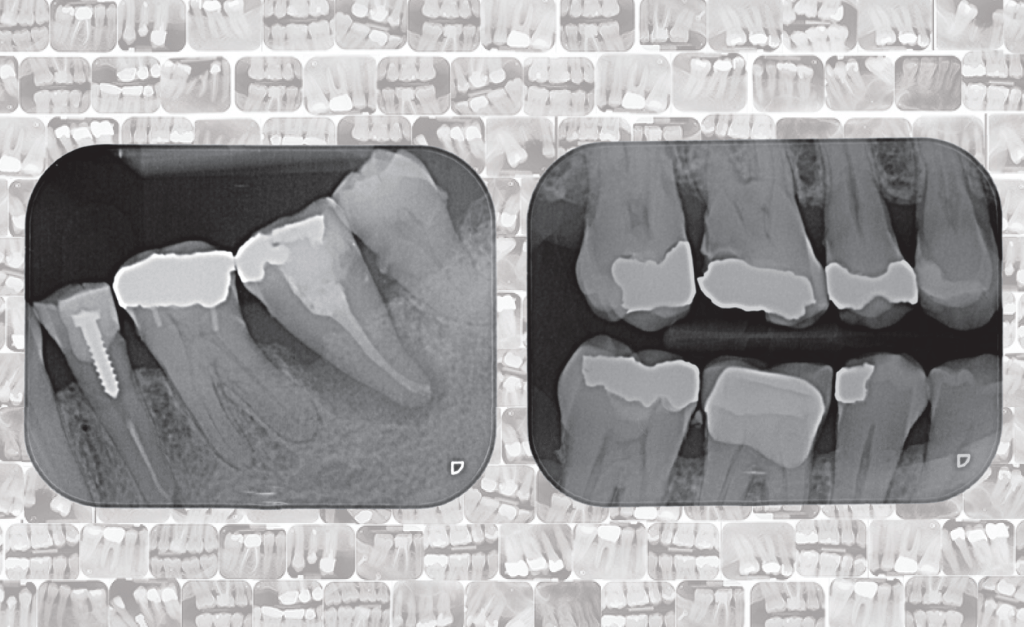

Dental Disease Detection

DENTAL RADIOGRAPHY IS an essential tool for the diagnosis of dental diseases, however, the analysis of the x-ray radiographs produced is a time-consuming and error-prone process. The Dental Disease Detection project is led by a collaboration of researchers, practitioners, and computer scientists at the University of Surrey, the London School of Medicine and Dentistry, and the Royal Surrey County Hospital. Their aim is to improve disease identification through the development of automatic approaches to spot signs of disease in dental radiographs.

The research team behind the Dental Disease Detection project are interested in automatically identifying common dental diseases; tartar, tooth decay and gum disease. It is important to identify and treat all of these diseases quickly, as they can cause significant problems such as bone loss, which is irreversible. However, the signs and symptoms of dental diseases can be hard to spot, making these conditions difficult to diagnose without inspection of a dental radiograph. Zooniverse volunteers are helping to improve the automatic identification of these diseases by drawing ‘bounding boxes’ (rectangles) on radiographs to mark the location of indicators of gum disease, tooth decay and plaque.

Image credit: Dental Disease Detection Project